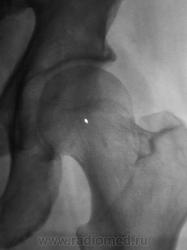

!. Давайте попробуем, тогда объяснить тень на фоне головки бедренной кости, помеченную стрелками и выделенную в круг. Что это...?

Зона препараторного обызествления(с сопутствующей ей линией просветления)...т.е. - изменения по бывшей зоне роста...пациент то не особо и стар...

Нет, он еще не старик, ему 67 лет, но крепкий мужчина.

А как расценить линию, помеченную стрелочками?

То же самое, но по отношению к основанию большого вертела в условиях отведения...как мне кажется